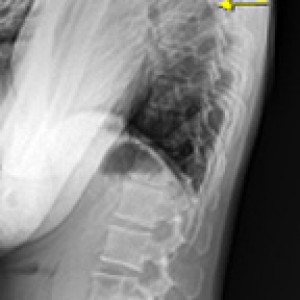

Before & After

해당 사진은 수정없는 실제 치료사진입니다.

환자의 치료결과는 환자의 상태, 치료방법 등에 따라 차이가 발생할 수 있습니다.